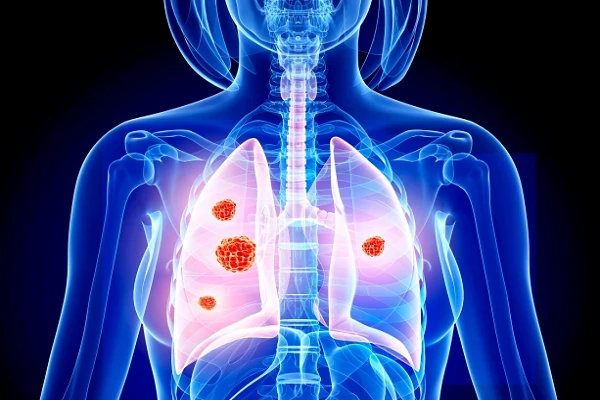

Đặc biệt là bệnh ung thư phổi rất khó phát hiện trong giai đoạn đầu. Ảnh: SCC.